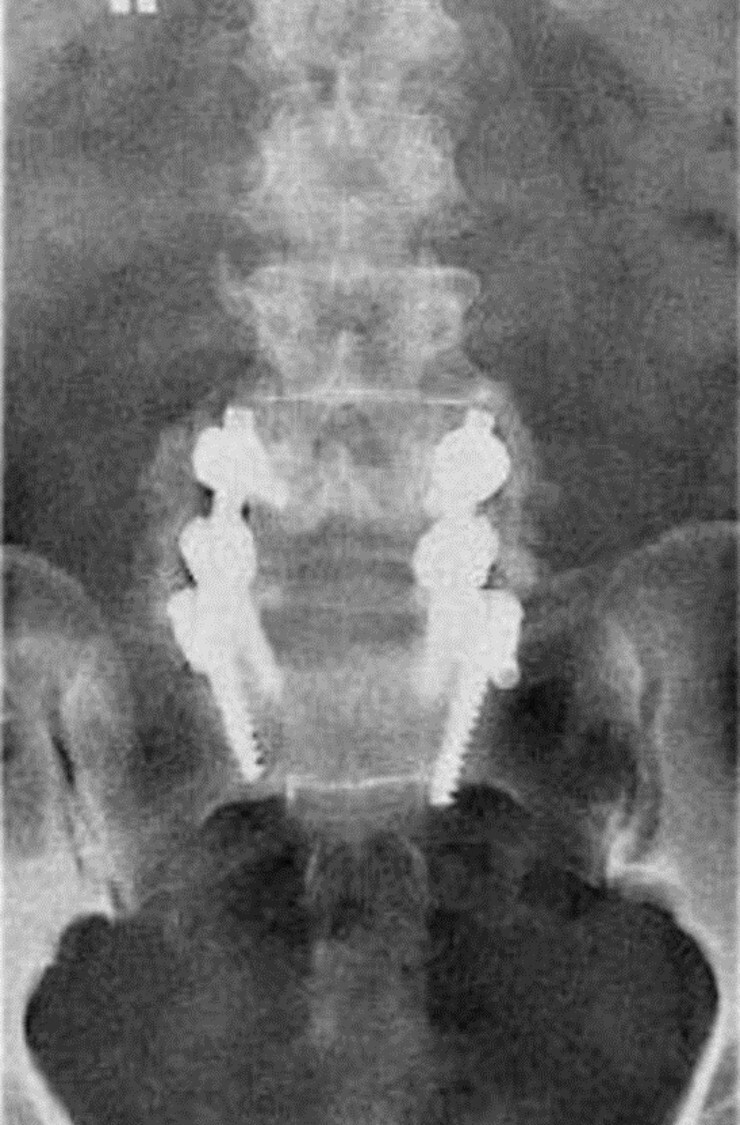

Q

Aside from the surgically implanted hardware, what artifact is seen in the attached image?

A

Quantum mottle from underexposure